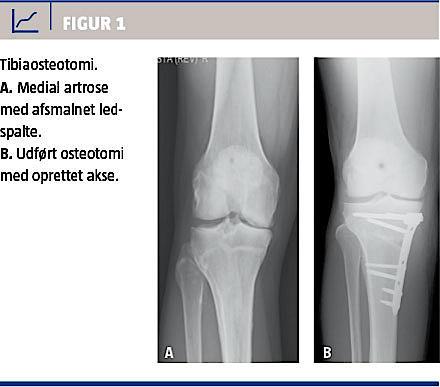

Moderne revisionssystemer er modulære, således at protesen kan opbygges i forhold til tab af knogle og ledbånd, og ledlinjen kan genskabes [25, 27]. Et stort knogletab (metafysært) kan i dag håndteres med specielle proteser [28, 29]. Alternativer til revision er bandagering (instabilitet og smerter), artrodese (manglende funktion af strækkeapparatet), og ved infektion anvendes livslang supprimerende antibiotika eller femuramputation [30]. Figur 2 viser revisionsalloplastik (roterende hængselknæ med tibiaaugmentation og trabekulær metalcone).